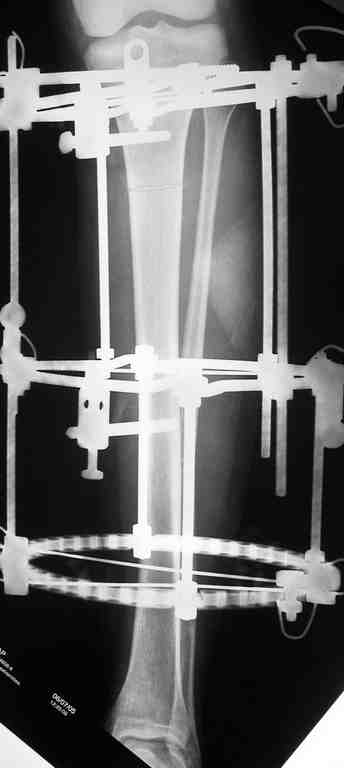

В верхнем ряду показаны рентгенограммы до, после коррекции и после снятия аппарата Илизарова.

On the upper row the X-rays of lt leg before correction, after correction and after apparatus removal have been showed.

В нижнем ряду представлены два снимка после коррекции деформации правой голени. Видно, что качество коррекции не зависит от квалификационного наложения аппарата Илизарова, что было специально произведено для проверки работы программы.

Lower two X-rays – rt leg after deformity correction. As you can see the quality of correction does not depend of placement of Ilizarov Apparatus